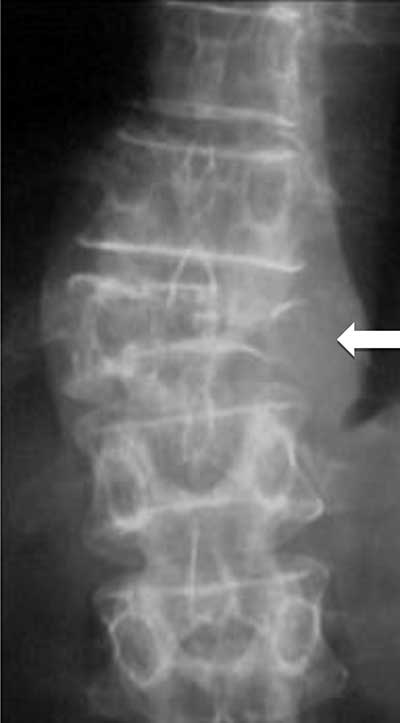

Figure 10

Multiple myeloma. Plain radiograph of spine shows an osteolytic lesion with cortical breakthrough, vertebral collapse and soft tissue mass (arrow).